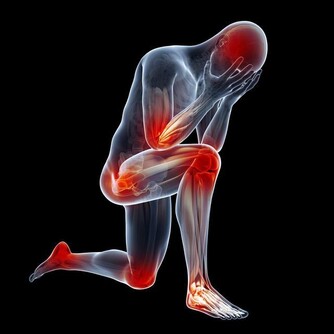

女性更年期雌激素下降的緣故

開頭我們就說了,來者大多是中年女性,這就不得不考慮性別和年齡兩個重要因素,我們自然而然會想到絕經和更年期。45-55之間的女性,逐漸發胖、衰老,體內的鈣質流失,關節負擔越來越重,出現了病理性改變,其實,不僅是手指,患者的膝蓋、肩膀、腰椎都可能受此影響。